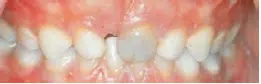

![Mund hvor fortand er blevet blå](https://gladsaxe.dk/i/MOLIRIMEDIA/b271f950-d433-472f-d508-08dc36def874?width=800)    ![Mund der viser en tandbyld over fortanden](https://gladsaxe.dk/i/MOLIRIMEDIA/d1da5415-c3f8-4ca2-d55b-08dc36def874?width=800)

På det første billede er en tand som har været slået og er blevet mørk. På det andet billede er der kommet en tandbyld ved en tand, som er slået. Dette er tegn på infektion. Det er vigtigt, at I henvender jer til tandklinikken.